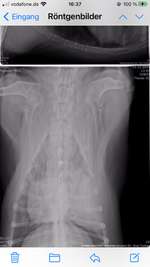

Mandelentzündung oder doch etwas anderes?

Meine 9 Monate alte fr.Bulldogge hat seit einer Woche Nasenlaufen, Probleme beim schlucken, erbrechen ( visköser schleim mit leicht blutiger Farbe ) und Abgeschlagenheit. Er nimmt nun seit 4 Tagen Antibiotika aber wir sehen keine Verbessrung. Er isst mittlerweile kaum bis nichts mehr, und ...